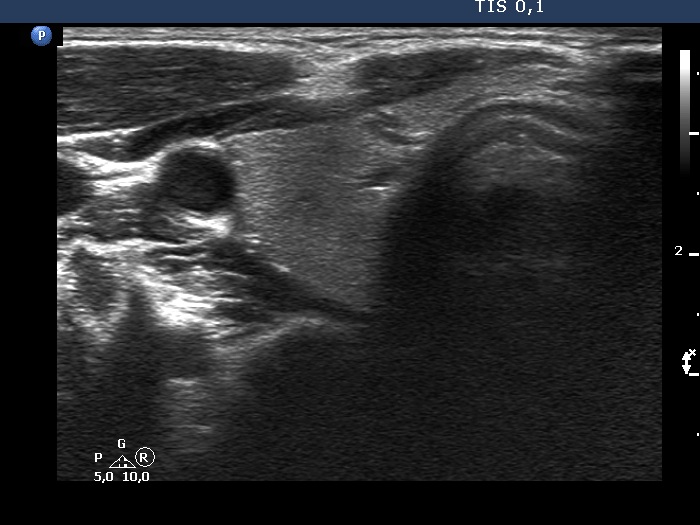

Introduction - case 1326 (ultrasonographic picture 2)

Right lobe, longitudinal scan

Right lobe, another transverse view. In this image, the area is more pronounced.